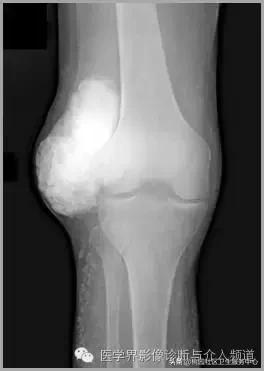

半月板钙化